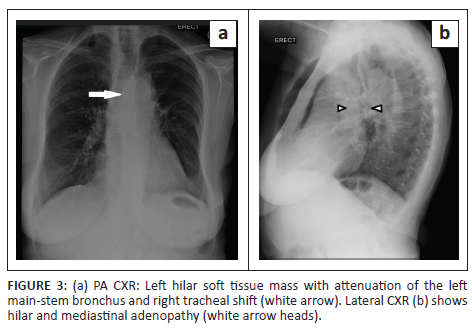

A posteroanterior chest radiograph performed at presentation revealed a left hilar mass with attenuation of the left main-stem bronchus and accompanying contralateral mediastinal shift (Figure 3). Post-contrast staging chest CT (Figure 4) showed an infiltrative, central, trans-spatial mediastinal mass encasing the left main-stem bronchus, left and right main pulmonary arteries and descending aorta. Abdomino-pelvic CT revealed multiple enhancing soft tissue mural lesions in the urinary bladder - consistent with metastases - the largest was located at the bladder base, with a similar lesion located anteriorly - in the space of Retzius - (Figure 5a), and complicated by right-sided hydro-uretero-nephrosis because of infiltration of the right vesico-ureteric junction (VUJ) by the largest deposit (Figure 5b & c). There was no abdominopelvic nodal or solid organ metastatic disease. No enhancing nodules were present in the right renal pelvis. The axial and appendicular skeletal elements were clear of metastases.